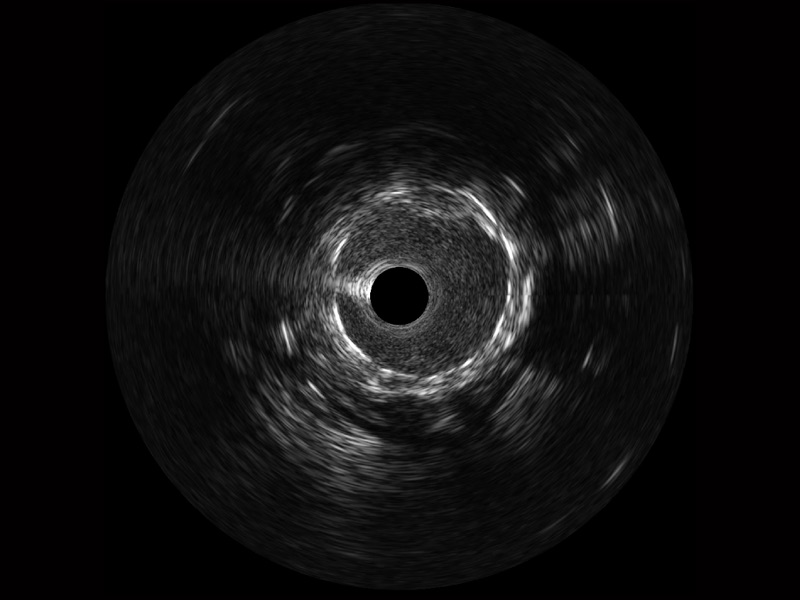

乐玩lewin国际超宽频成像技术覆盖20-80MHz1或20-90MHz2频率范围, 提供优异的分辨力同时也保证充足的穿透深度

对比传统IVUS导管成像,乐玩lewin国际宽频IVUS图像的近场支架梁显影更细腻,远场中膜外血管仍清晰可辨,兼顾远中近,兼顾分辨力与穿透深度